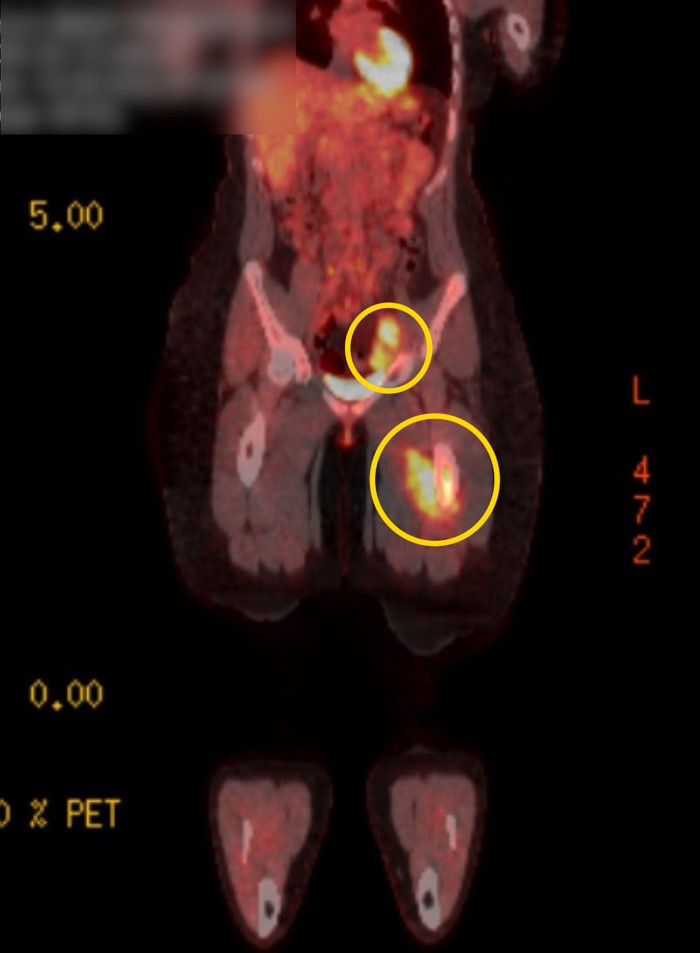

Life-Altering MRI Scan: Unveiling Stage Four Ewing Sarcoma

It was at this critical juncture that a doctor decided to conduct an MRI scan, a decision that would ultimately change the course of her life. The results of the scan revealed two tumors: one located in her femur and another in her groin.

The diagnosis was stage four Ewing sarcoma, a rare and aggressive type of soft tissue cancer that primarily affects children and young adults. The revelation of her cancer diagnosis came as a profound shock, not only to Bailey but also to her family and friends.